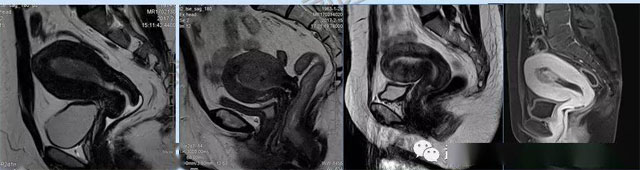

婦科疾病常常讓女性陷入了焦慮。主要是這類疾病婦女有難言之隱,癥狀隱匿,病情復雜。磁共振體檢車的金光火眼能力可以破解各種婦科難題。哪些情況需要使用磁共振檢查,檢查過程是否有不適。這些都是可以解決的。例如子宮常見疾病的磁共振診斷。

磁共振VS傳統(tǒng)檢查:有這些優(yōu)勢?無輻射安全系數高,磁共振沒有電離輻射,適合備孕跟孕婦檢查。它對軟組織有高清的成像效果,可以清晰的看到子宮各層的結構??梢宰R別細小的肌瘤,早期的癌癥腫瘤。可以發(fā)現其他設備難以檢查到的深部子宮內膜異位結節(jié)。多序列成像和增強掃描檢查,判斷腫瘤的良性準確率高達90%以上。